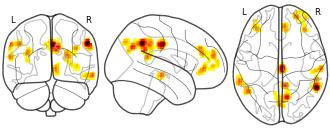

License information was derived automaticallyDescriptionCertain-Threat Convolved Block 2 minus Certain-Threat Convolved Block 3 (unthresholded)

The Maryland Threat Countdown (MTC) paradigm is a well-established, fMRI-optimized adaptation of temporally uncertain-threat assays that have been behaviorally, pharmacologically, and psychophysiologically validated in rodents and humans. It takes the form of a 2 (Valence: Threat/Safety) × 2 (Temporal Certainty: Certain/Uncertain) repeated-measures, randomized event-related design. We capitalized on the temporally-extended threat-anticipation periods (8.75-30 s, mean = 18.75 s) of the MTC paradigm by modeling temporal dynamics in a more granular manner than before. For continuity with previous research, we performed an initial analysis using a single, variable-length rectangular input function (boxcar) for each anticipation epoch. In our theory-inspired model, we applied three input functions to each anticipation epoch: a brief, transient input function time-locked to anticipation epoch onset, an overlapping variable-length rectangular input function to model sustained activity spanning the entire anticipation epoch and a short, overlapping rectangular input function (6.15 s duration) time-locked to the terminal end of anticipation epochs to capture phasic surges during the ‘circa-strike’ phase. Each of the three input functions was convolved with a canonical HRF. For a second modeling approach, we took a piecewise approach to estimating BOLD magnitude in the temporal domain. For each anticipation period, 2-5 contiguous mini-blocks (6.25 s duration ‘boxcars’) were convolved with a canonical HRF. Findings point to a core neural ‘threat’ system that shows sustained activity across temporally uncertain threat and rapidly assembles in the face of certain-and-imminent threat.